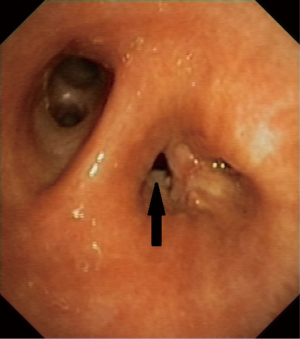

The bronchoscopic placement of the device was performed using combined rigid-flexible bronchoscopy. General anaesthesia was established, a rigid bronchoscope was introduced into the trachea and jet ventilation was initiated. A flexible bronchoscope (Type BF 1T-180; Olympus, Hamburg, Germany) was introduced and the BPF was located in the bronchial stump (Figure 1). Using bronchography with contrast agent application, the anatomy and size of the fistula was analyzed. The size of AD was calculated using computed tomography and direct measurement during bronchoscopy. The size of AD was chosen according to the size of the fistula and the diameter of the bronchial stump, so that the device completely covered the fistula and also fit into the stump (Figures 2,3). The delivery catheter with the loaded device was introduced through the rigid bronchoscope and the device was deployed into the BPF under direct endoscopic vision and fluoroscopic guidance. Once placed correctly, the device was released by unscrewing the attached cable. To verify the complete occlusion of the BPF, a second bronchography with contrast agent application was performed (Figure 4). After removal of the bronchoscope, the patient was transferred into the recovery room and a standard X-ray was performed.